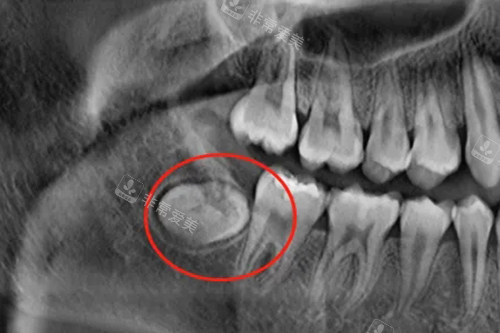

3. 完全埋伏阻生智齿拔除(高难度):

智齿完全深藏于牙槽骨内,需借助影像学定位,用专科器械去骨后才能取出,对医生技术和设备要求较高。

中低位完全埋伏智齿拔除:1800-2500元起

神经管高危型完全埋伏智齿拔除:2500-3000元起

此类手术耗时通常在1小时以上,部分情况需填充骨粉保护牙槽骨,价格包含术前定位、术中去骨及术后护理等相关费用,是所有类型中收费更高的一档。

阻生智齿埋伏牙片示意图